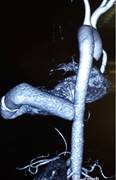

Khó khăn lớn nhất gặp phải khi thực hiện phẫu thuật cho bệnh nhân là không có vật liệu tiêu chuẩn để làm cầu nối. Đó là bộ vật liệu bao gồm ống nối cho mỏm tim, van tim nhân tạo và ống mạch nhân tạo. Các vật liệu này được thiết kế riêng cho phù hợp với việc luồn vào mỏm thất trái và đường đi của nó đến động mạch chủ xuống để không làm hẹp các miệng nối, đoạn gấp khúc và đảm bảo dẫn lưu đủ cung lượng tim [4]. Hiện ở Việt Nam chưa có bộ sản phẩm này trên thị trường. Để giải quyết vấn đề trên, chúng tôi sử dụng ống mạch nhân tạo số 27 để nối với mỏm thất trái, nối một ống mạch nhân tạo khác có gắn van (đầu ngoại vi) vào động mạch chủ xuống đoạn ngang mỏm tim. Sau đó hai đoạn này được nối lại với nhau để tạo thành một cầu nối tắt có van cho dòng máu di chuyển một chiều từ mỏm thất trái xuống động mạch chủ (Hình 4c,d,e,f,g). Lý do để chọn đoạn mạch có cỡ lớn như vậy là đề phòng trường hợp gấp khúc cầu nối dẫn đến gây hẹp và dẫn lưu không hết thể tích tống máu của thất trái. Kết quả chụp cắt lớp vi tính đa dãy đầu dò sau mổ cho thấy vẫn có tình trạng gấp khúc cầu nối trước và sau van nhân tạo (Hình 5) nhưng trên siêu âm thì chênh áp qua các chỗ này là không đáng kể cho thấy việc lựa chọn vật liệu là phù hợp.